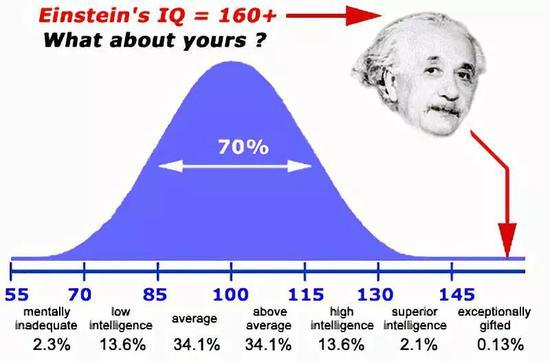

人类IQ平均值约为100

患病年轻成人的平均智商只有50,相当于8、9岁孩童的智商值。

因此唐氏综合征患者通常需要额外接受更多的教育。

但即便如此,他们也很少能在高中毕业后继续完成高等教育。

在美国,只有20%的患者能够获得工作岗位。

更多的人则需要额外的财务和法务支援才得以生存。